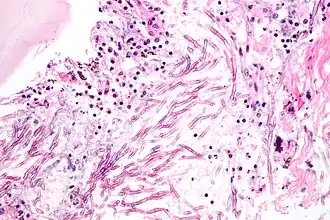

Mycosen of schimmelziekten zijn infecties veroorzaakt door parasitaire schimmels. Ze kunnen zowel bij mensen, dieren als planten voorkomen.

Candida is een geslacht van hoofdzakelijk facultatief parasitaire schimmels. Een veel voorkomende soort is Candida albicans op de slijmvliezen. Deze schimmel komt meestal voor in gistvorm. Onder bepaalde omstandigheden neemt de schimmel echter hormonen op. Deze situatie komt onder andere voor bij de zwangerschap en bij het ingaan van de menopauze. De schimmel wordt meercellig en maakt het slachtoffer dan behoorlijk ziek.